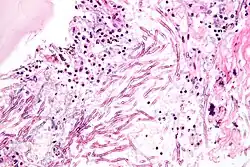

Wachsen eingeatmete Aspergillus-Sporen in der Lunge aus und sind nicht auf eine kompakte Kolonie beschränkt, entwickelt sich eine akute Aspergillose. In der Lunge bilden sich Hyphen und anschließend Myzel, das schließlich über die Blutbahn im gesamten Körper streut. Es bilden sich Metastasen an den Organen und im zentralen Nervensystem. Bei erwachsenen Menschen mit intaktem Immunsystem kommen akute Aspergillosen nicht vor, bei Kindern sind sie sehr selten. Immunsupprimierte Patienten, zum Beispiel nach einer Knochenmark- oder Stammzelltransplantation oder AIDS-Patienten erkranken aber nicht selten daran. Die invasive Aspergillose ist eine gefährliche Infektion mit einer hohen Letalität im Bereich zwischen 50 % und 95 %.[17] Vor allem Vögel erkranken häufig an akuten Aspergillosen. Bei Küken von Haushühnern wird die Erkrankung Aspergillus-Pneumonie genannt und führt immer wieder zu Massensterben in Zuchtanlagen. Auch bei Wildvögeln treten immer wieder Epidemien auf und wurden unter anderem bei Afrikanischen Straußen (Struthio camelus) und Silbermöwen (Larus argentatus) beobachtet. Bei Papageien (Psittaciformes) treten durch Aspergillus verursachte Lungen- und Luftsackmykosen auf.[18] Unter Säugetieren sind Erkrankungen bei Lämmern häufig, bei Hausrind-Kälbern dagegen sehr selten. Epidemien traten bei Kaninchen und Meerschweinchen (Caviidae) auf. Bei Pferden (Equus) sind vor allem Luftsackmykosen gefürchtet. Diese werden zumeist durch Aspergillus fumigatus, aber auch durch andere Aspergilli oder Pilze der Gattungen Penicillium oder Mucor verursacht.[19]